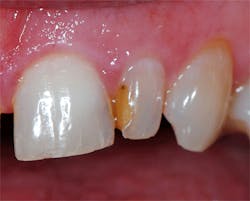

A 62-year-old female patient presented with the complaint of discoloration of a maxillary left lateral incisor. She reported slight, periodic sensitivity to cold on the tooth. Examination disclosed that an old composite restoration was "washing out" (figure 1). The treatment recommended consisted of replacing the defective composite with a new composite.

Figure 1: A defective composite was noted during a hygiene recall appointment, and the patient was advised it needed to be replaced.